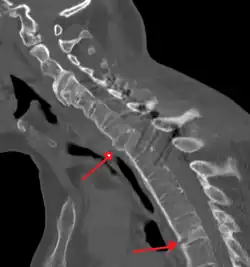

Lateral X-ray of the mid back in ankylosing spondylitis -

Lateral X-ray of the neck in ankylosing spondylitis -

The earliest changes demonstrable by plain X-ray shows erosions and sclerosis in sacroiliac joints. Progression of the erosions leads to widening of the joint space and bony sclerosis. X-ray spine can reveal squaring of vertebrae with bony spur formation called syndesmophyte. This causes the "bamboo spine" appearance. A drawback of X-ray diagnosis is the signs and symptoms of AS have usually been established as long as 7–10 years prior to X-ray-evident changes occurring on a plain film X-ray, which means a delay of as long as 10 years before adequate therapies can be introduced.[26]

Options for earlier diagnosis are tomography and MRI of the sacroiliac joints, but the reliability of these tests is still unclear.